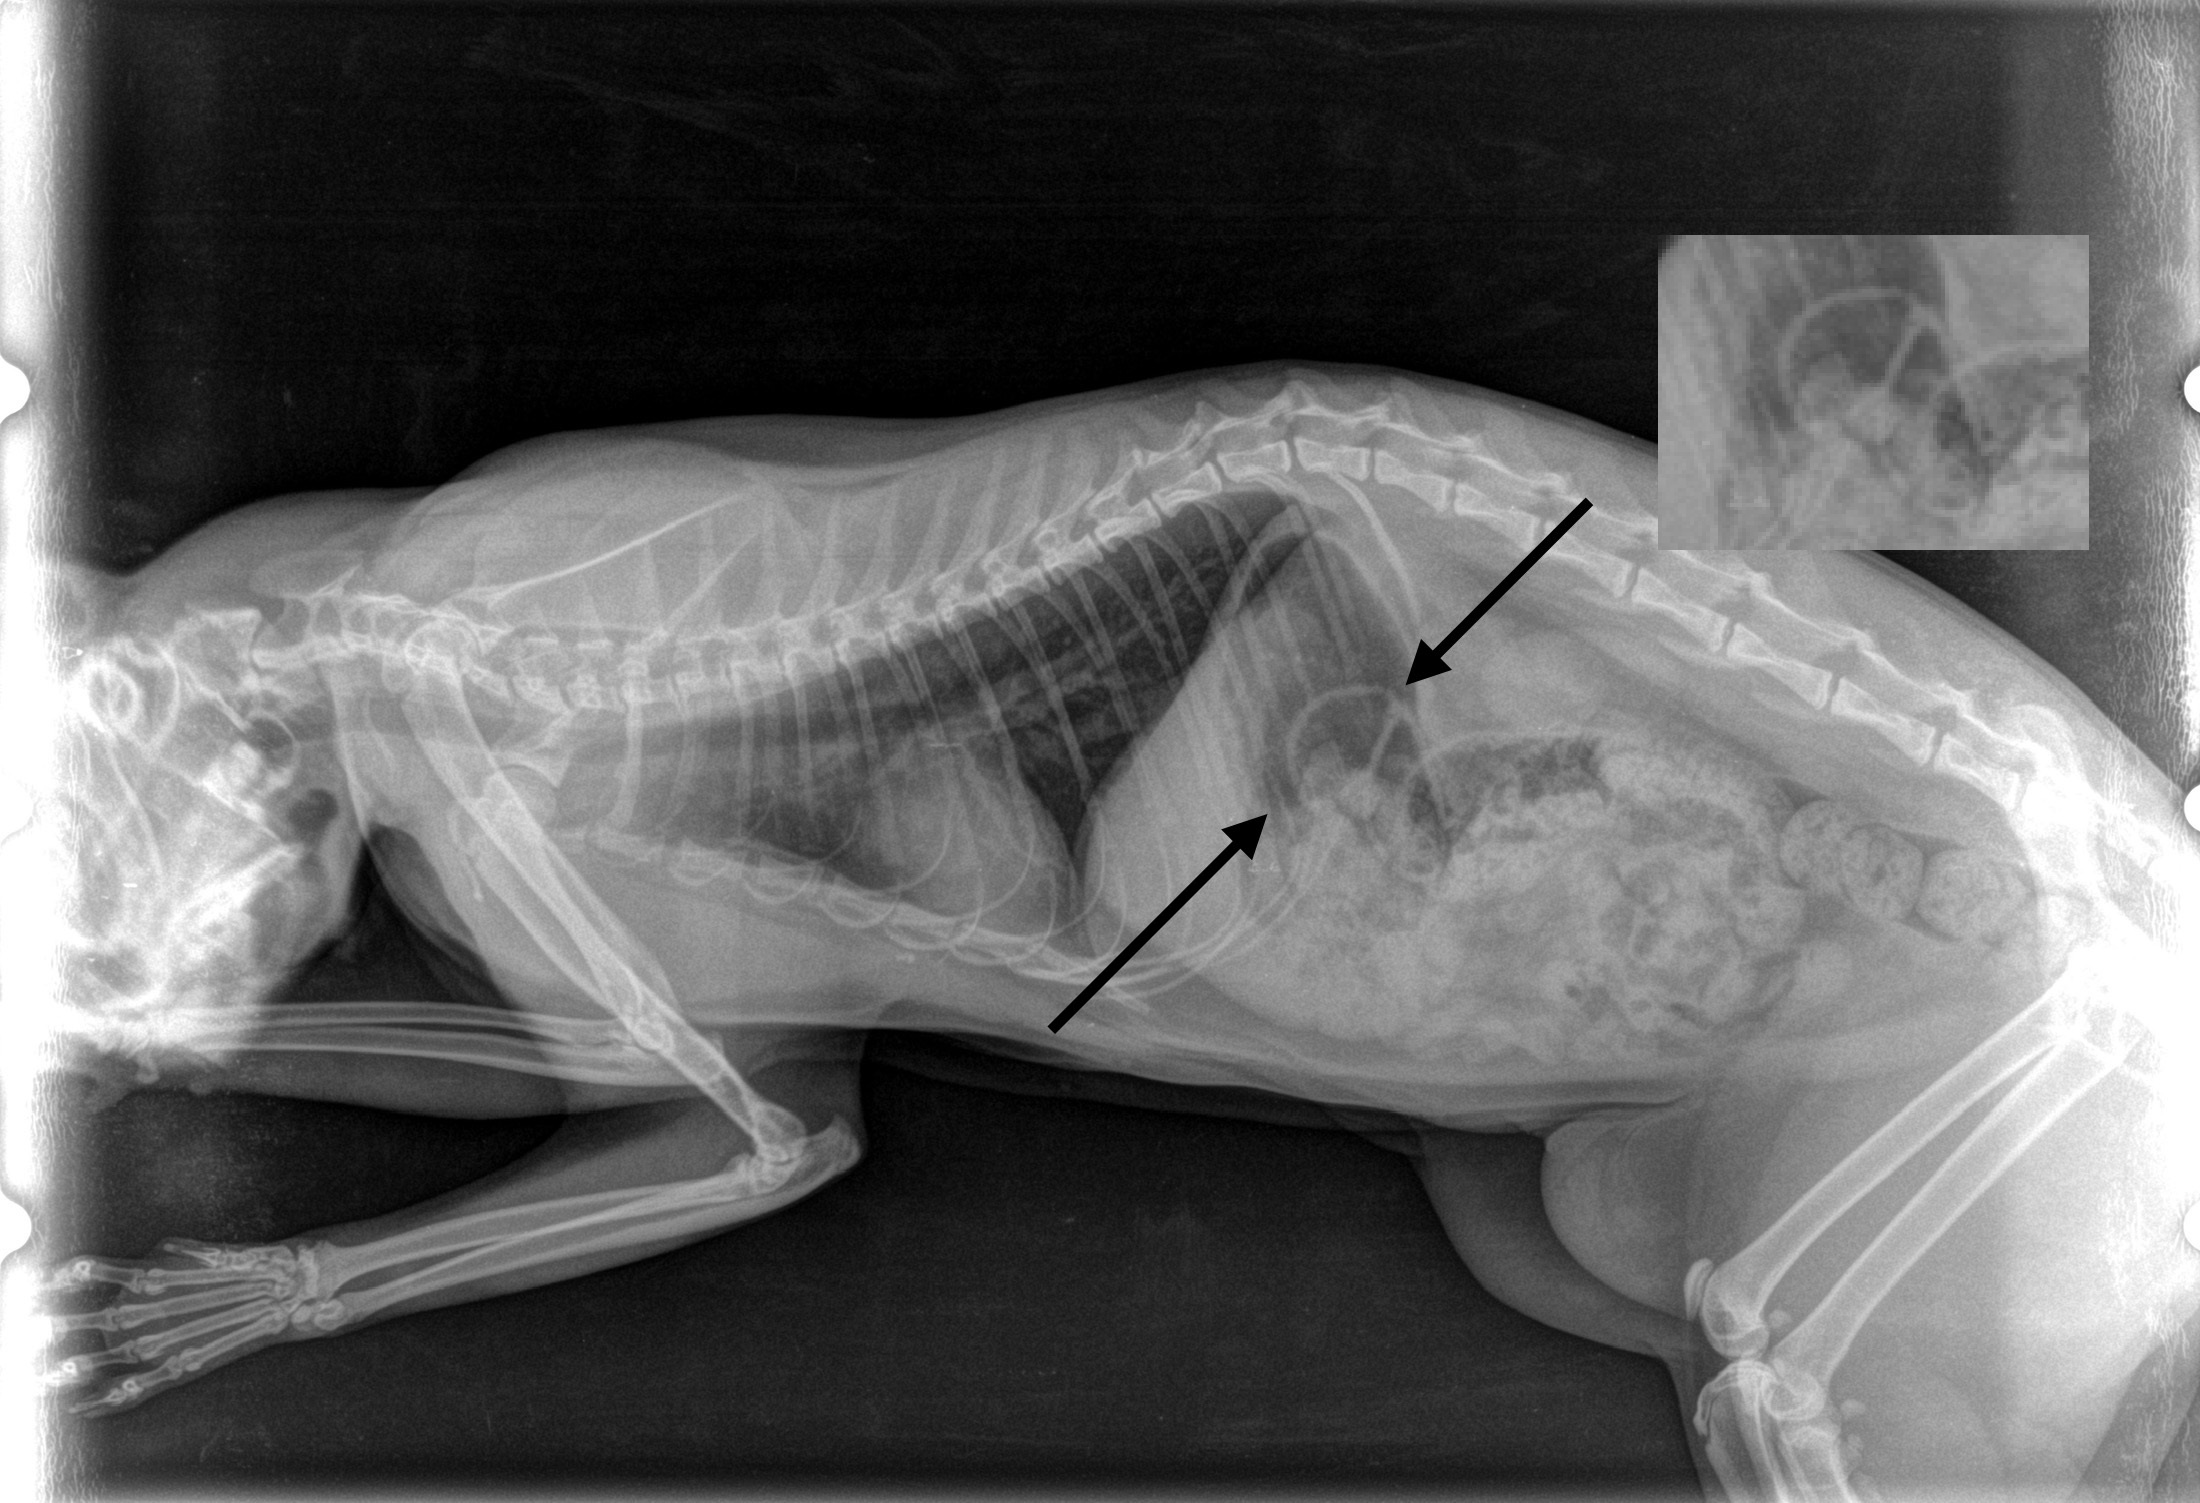

Když to majitelka zpozorovala, zavolala nám a domluvili jsme se na okamžitém příjezdu. Přítomnost gumičky v žaludku jsme si potvrdili rentgenem .